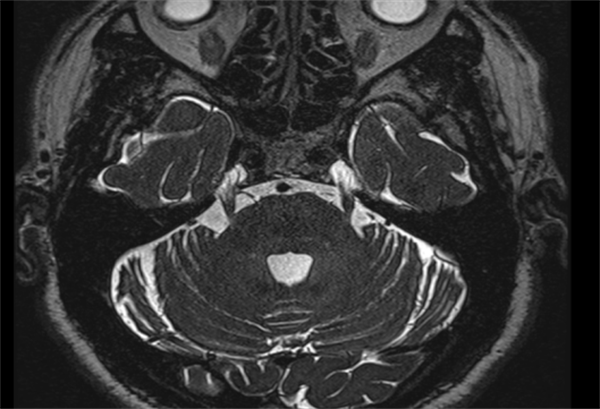

疼痛每个人都体会过,但号称“天下第一痛”的三叉神经痛却没几个人能懂。75岁刘大爷(化名)不幸得了右侧三叉神经痛,不敢说话,不敢吃饭,甚至痛不欲生。近日,捆绑调教 (简称捆绑调教 )杨超教授团队通过运用纯内镜下三叉神经微血管减压术,帮助患者解决疼痛烦恼。术后的刘大爷状态恢复良好,现在面部不疼,也能正常吃饭了。据了解,刘大爷长期饱受右侧面部疼痛的折磨。2021年,...